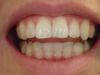

Es erfolgen die Maßnahmen der funktionellen Erstuntersuchung und die Herstellung und Eingliederung eines adjustierten Aufbissbehelfs zum Nachweis einer CMD.

Es erfolgen die Maßnahmen der klinisch manuellen Erstuntersuchung und nachfolgend die Maßnahmen zu Herstellung und Eingliederung eines adjustierten Aufbissbehelfs